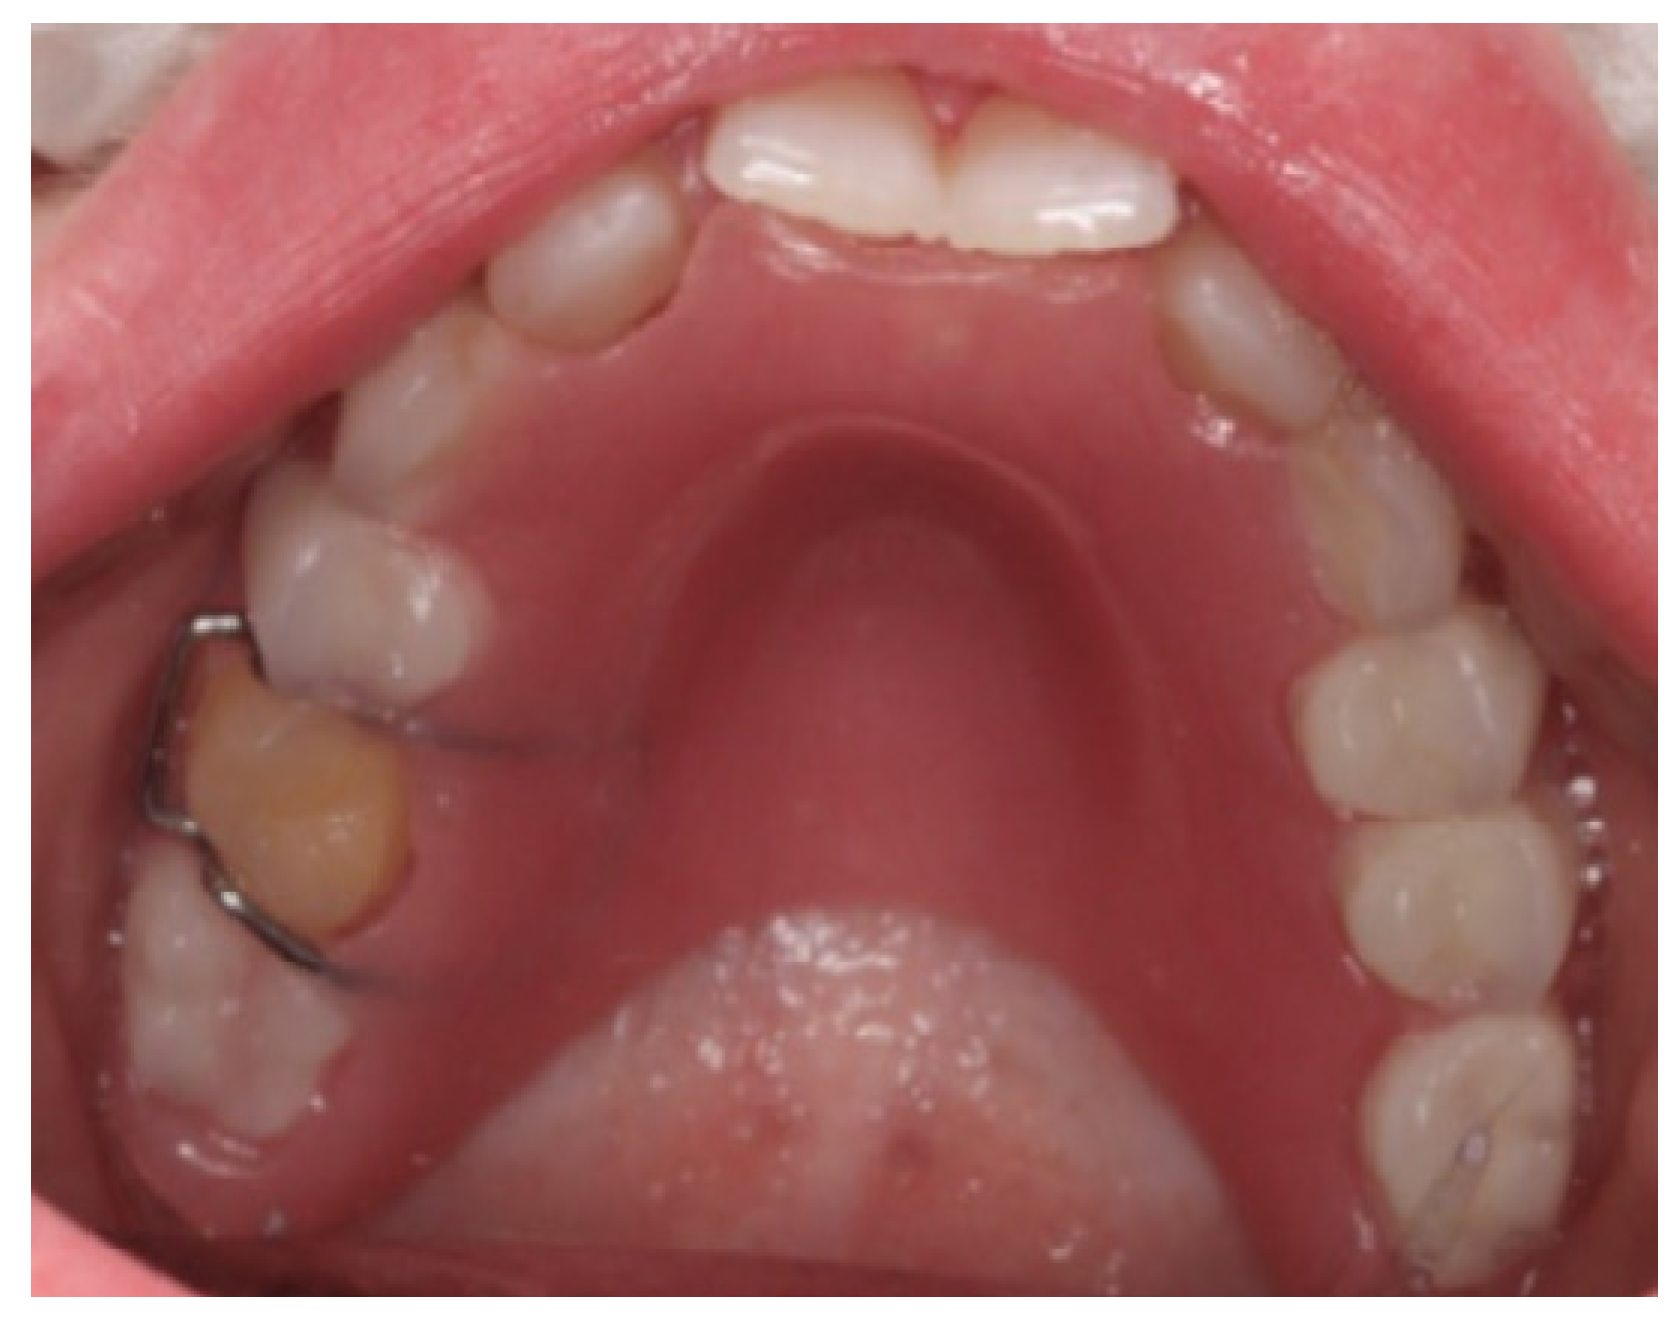

For the maxillary overdenture, the non-infected primary teeth and their remaining roots were kept, preserving the space and the alveolar bone. The trial setup confirmed optimal esthetics, phonetics, and a balanced occlusal scheme, which were deemed satisfactory by both the patient and the parent, and retention was enhanced by incorporating an Adam’s clasp on tooth UR5 and a C clasp on tooth UL2. The treatment in the mandibular arch involved the extraction of the sound lower incisors teeth due to Grade II mobility, followed by the delivery of an immediate removable denture. Retentive clasps were placed on primary molars 75 and 85 to improve stability. The immediate denture was intended as a temporary solution to maintain function and esthetics during the healing period. Once the soft tissue had adequately healed, a conventional removable partial denture was fabricated to provide a more definitive prosthetic option.

Post-insertion instructions included avoiding direct biting on the pontics for the initial 24 h and maintaining excellent oral hygiene, especially around the abutment teeth. The patient was reviewed one week, three months, and six months after cementation, with future follow-ups planned at regular intervals (Figure 7, Figure 8 and Figure 9).

Figure 8. Intra-oral photograph, upper occlusal arch.